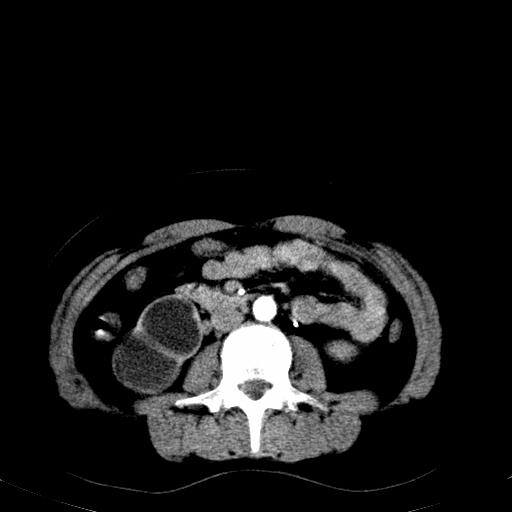

患者体检发现右肾体积增大,怀疑右肾积水

右肾重度积水,以肾盏积水明显,有分隔,上段输尿管轻度扩张,管壁增厚,考虑肾结核可能,请结合尿检查,胸部拍片排除肺结核。

右肾重度积水,建议ct向下扫描或逆行造影,左肾及左输尿管结石 .

患者尿常规正常,b超未发现明显结石,自身也无明显感觉异常。

请问多囊肾与肾积水怎么鉴别